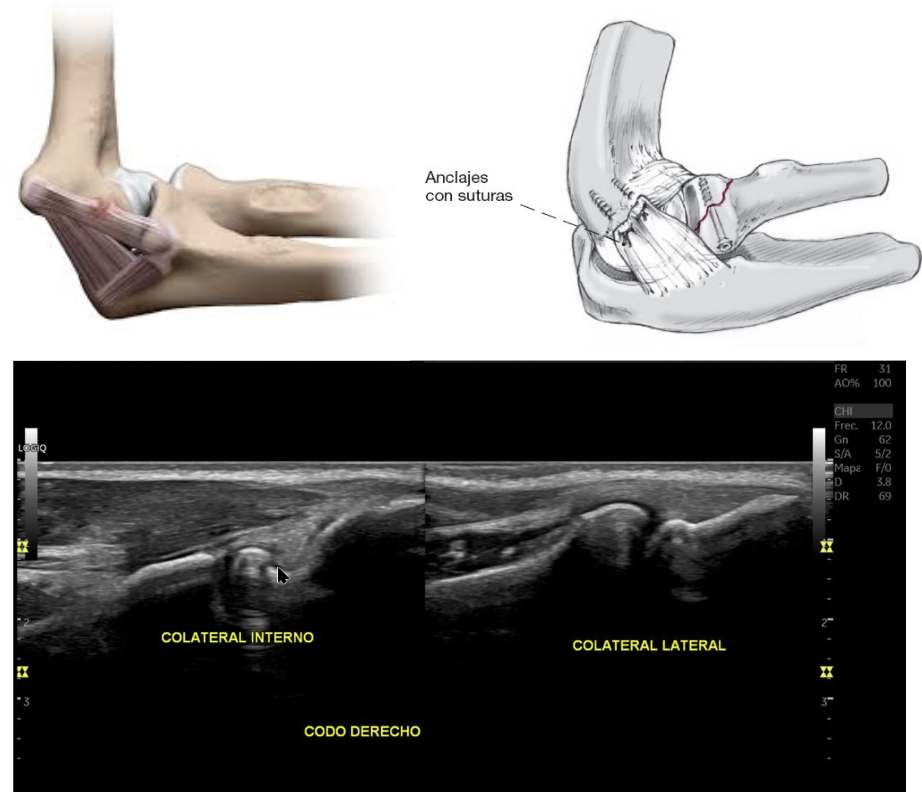

Cirugía de Tommy John: Esta cirugía se hizo famosa porque se realizó al reconocido jugador de Baseball “Tommy John” en la que se reconstruye el ligamento colateral ulnar a nivel del codo debido a lesión o inestabilidad.

Lesiones de ligamentos colaterales del codo: Los ligamentos colaterales del codo son el interno (UCL o ligamento colateral cubital) y el externo (RCL o ligamento colateral radial) y estos ayudan a la estabilidad en el plano coronal; es decir evitan el movimiento lateral de la unión del cúbito - radio y húmero distal. Pueden sufrir lesiones si existen fuerzas que sobrepasan su resistencia, las fuerzas en varo o valgo. En estos casos es posible realizar ecografía o ultrasonido para detectar su lesión, o hasta una resonancia magnética.